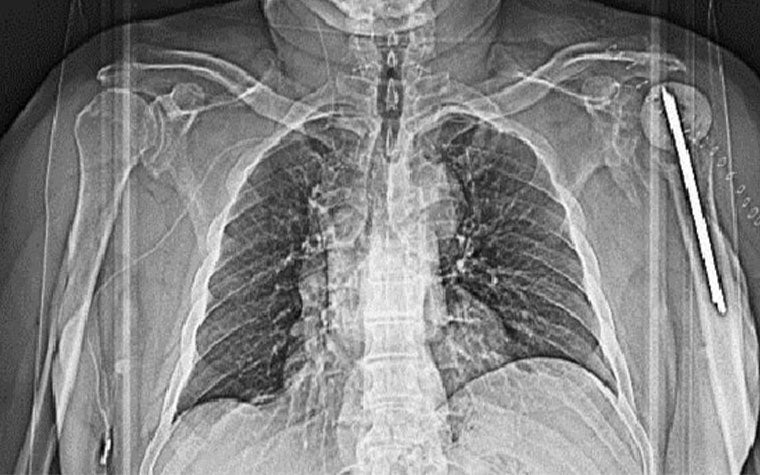

Left: Pre-op X-ray showing the old implant in the patient’s left shoulder. Right: Prof. Dr. Stefaan Nijs, Chairman of Trauma Surgery at Leuven University Hospital

The postoperative report issued one and a half years after the procedure showed that the implant and screws were still in place. There are limited orientation and position differences between the analyzed planned position and the actual outcome.